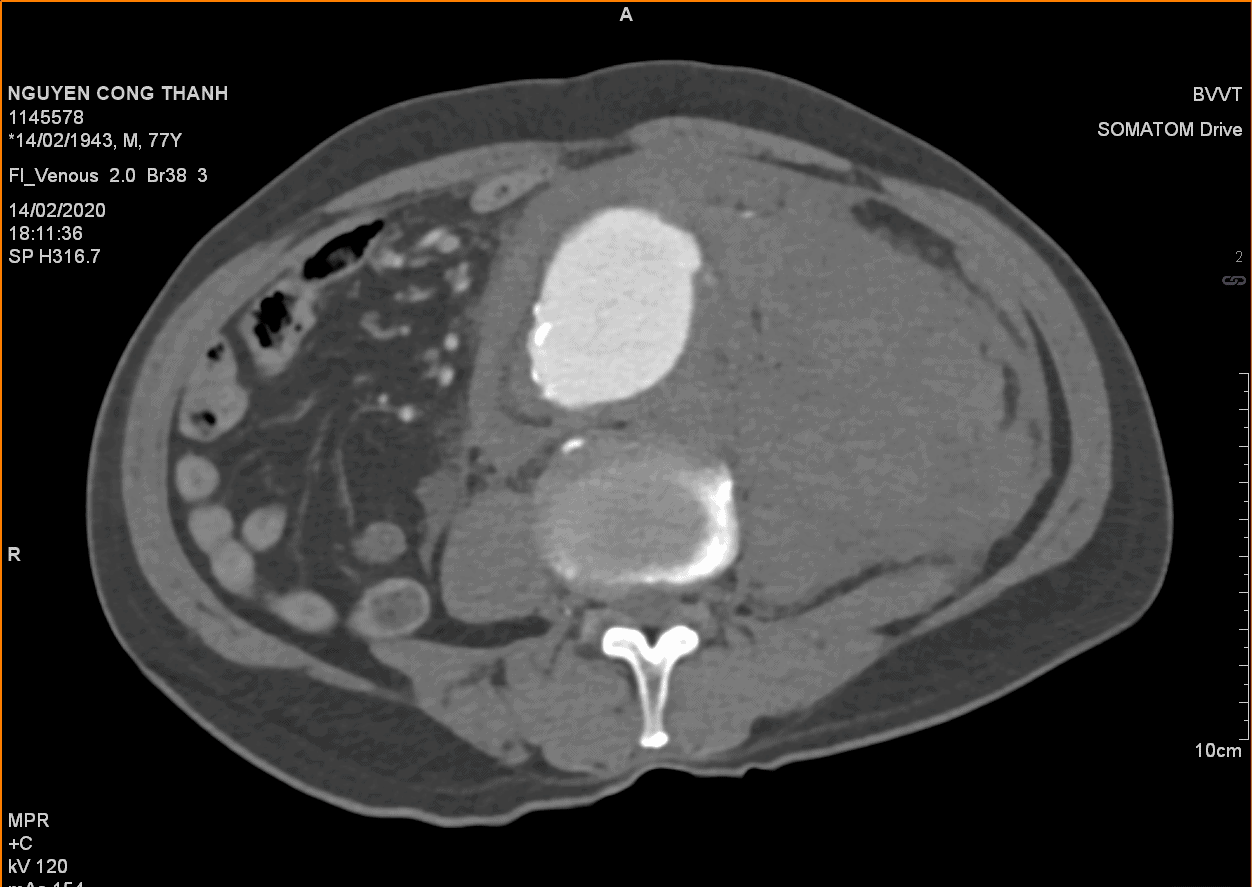

Vỡ phình ĐM chủ bụng

» Thông tin: Nam giới – 77 tuổi.

» Lâm sàng: Đau bụng cấp.